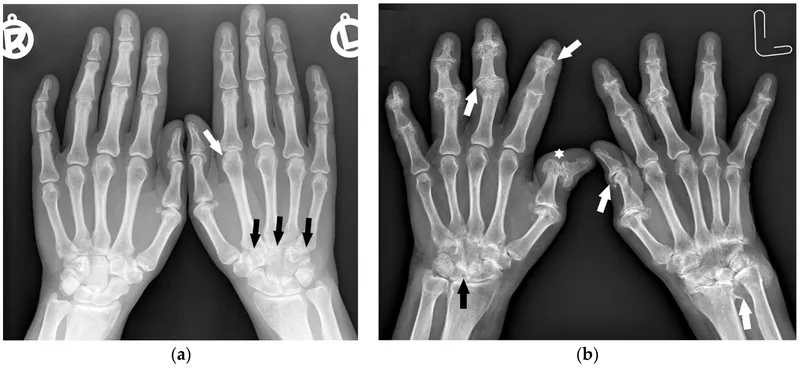

- Rheumatoid Arthritis (RA): Chronic, autoimmune, systemic inflammatory disease targeting synovial joints.

- Pathogenesis: Immune attack (T/B cells, Mφ) + cytokines (TNF-α, IL-1, IL-6) → synovitis, pannus, joint destruction.

⭐ Early aggressive treatment with DMARDs is crucial to prevent irreversible joint damage and disability in RA.